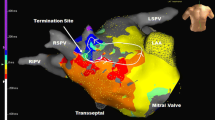

The SuperMap algorithm successfully identified the arrhythmogenic substrate in all 7 patients (100%). Three patients (43%) exhibited focal tachycardia mechanisms. One patient presented with a focal tachycardia with the earliest activation in the anteroseptal region of RSPV with a cycle length (CL) of 270 ms (Fig. 3). Ablation in the earliest site (−35 msec before P wave) led to immediate termination of the arrhythmia. Isoproterenol infusion led to the induction of a second focal tachycardia located in the anterior wall of the LA (CL = 320 ms). Ablation in the earliest site led to conversion to sinus rhythm. Pharmacological stimulation could not induce further arrhythmias in this patient. In another patient, a focal tachycardia at a CL of 400 ms was localized on the posterior wall in proximity of the LIPV. Ablation led to conversion to sinus rhythm. No further arrhythmia was induced following ablation. The last patient presented with a focal tachycardia originating from the interatrial septum in proximity of the fossa ovalis at a mean CL of 235 ms. Applications on the left side of interatrial septum in this location led to the interruption of the arrhythmia. No further arrhythmias were induced.

The remaining 4 patients (57%) exhibited reentrant tachycardias. In 3 patients the SuperMap algorithm detected mitral isthmus-dependent flutters (Fig. 4) with a tachycardia CL of 240, 270, and 420 ms, respectively. A mitral isthmus line was performed connecting the LIPV to the mitral annulus in a posterolateral position. In 1 patient additional epicardial applications were needed in the CS in order to terminate the tachycardia. Bidirectional block could be documented in all cases along the lines.

Mitral isthmus dependent atypical flutter: Panels (a), (b), (c), (d), (e), and (f) represent the electrical activation projected on the LA anatomy in different time steps throughout the full CL of the counter clock wise mitral isthmus dependent AFL. Yellow arrow is indicating the wave front. All panels show a LAO view of the LA